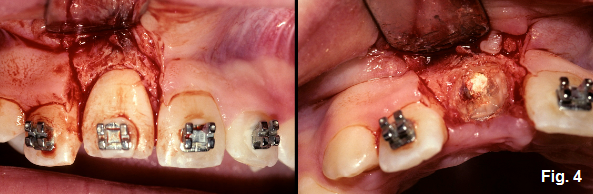

It was at this time that it was decided to remove the ankylosed tooth prior to the continuation of growth. Mamlgren et al. described a technique in a 2006 paper that discussed the use of decoronation in circumstances such as this. (Fig. 3)

Rather than remove all of the tooth fragments, decoronation removes the crown of the tooth approximately 1mm below the osseous crest. (Fig. 4)